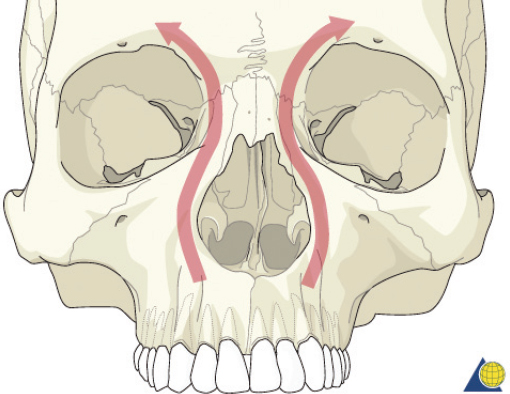

The nasoorbitoethmoid complex represents the confluence of the nasal, lacrimal, ethmoid, maxillary, and frontal bones. It constitutes the underlying support and symmetry for the central midface. The primary vertical buttress of the nasoorbitoethmoid complex is the frontal process of the maxillary bone ( Fig. 63.49 ). The primary horizontal buttresses are the superior and inferior orbital rims. Violation of these buttresses due to nasoorbitoethmoid fractures may result in longterm sequelae including nasal deformity, telecanthus, enophthalmos, midface retrusion, epiphora, CSF fistula, anosmia, sinusitis, and blindness. The medial canthal tendon arises from the anterior and posterior lacrimal crests as well as the frontal process of the maxilla. It surrounds the lacrimal sac and diverges to become the pretarsal, preseptal, and orbital orbicularis oculi muscle ( Fig. 63.50 ). The medial canthal tendon (and its bony attachment) maintains the intercanthal distance and is the focal point of nasoorbitoethmoid fracture repair. Normal intercanthal distance is 30 to 35 mm. This is equivalent to the width of the alar base and onehalf the interpupillary distance ( Fig. 63.51 ).

Injuries to the nasoorbitoethmoid complex can be difficult to diagnose, as they may be masked by facial edema. A complete head and neck examination should be performed including the brain, cervical spine, orbits, and presence of CSF leak. Both neurosurgery and ophthalmology consultations may be required. A high degree of suspicion must be maintained because failure to identify these injuries often results in deformities that are extremely difficult to repair secondarily. Physical findings suggestive of a nasoorbitoethmoid fracture include: (1) widening of the intercanthal distance greater than 30–35 mm; (2) blunting of the medial canthus and narrowing of the palpebral fissure width ( Fig. 63.52 ); (3) widening of the nasal dorsum; and (4) rotation, deprojection, and shortening of the nose. The integrity of the medial canthal tendon should be evaluated by carefully applying lateral tension to each lid. Normally, there will be a defined end point to the maneuver, without palpable motion at the canthal insertion ( Fig. 63.53 ). A periosteal elevator can also be inserted through the nose to apply lateral pressure in the same area. A lax medial canthal tendon, or medial orbital wall motion, is consistent with a nasoorbitoethmoid complex fracture. Telecanthus, enophthalmos, pupillary response, and extraocular muscle mobility should be assessed and documented. The degree of nasal or midface retrusion should be assessed. The surgeon should palpate the nasal dorsum at the nasion, rhinion, and tip ( Fig. 63.54 ). If there is significant lack of support along the entire nasal dorsum, an onlay calvarial bone graft will be required. Finally, thin cut (1–1.5 mm) CT scan with coronal, sagittal, and 3D reconstructions plays an important role in defining the pattern and extent of injury. The surgeon must assess the cribriform plate, frontal recess/sinus involvement, orbital integrity, degree of nasoorbitoethmoid complex comminution, and associated facial fractures. Characteristic radiologic findings include: (1) disruption and widening of the nasal dorsum in the coronal plane; (2) a “Y-sign,” occurring when the frontal process of the maxilla/lacrimal bone fractures at the insertion of the canthal ligament, resulting in a Y-shaped bone fragment ( Fig. 63.55 ); (3) depression of the nasal root; and (4) disruption of the frontal recess.